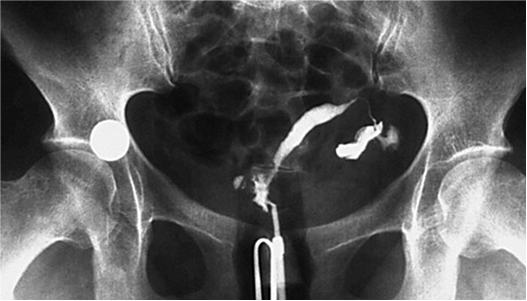

Histerosalpingografía:

Radiografía del útero y trompas de Falopio que utiliza medio de contraste para evaluar si hay obstrucciones que dificulten el paso de los espermatozoides o la implantación del embrión.